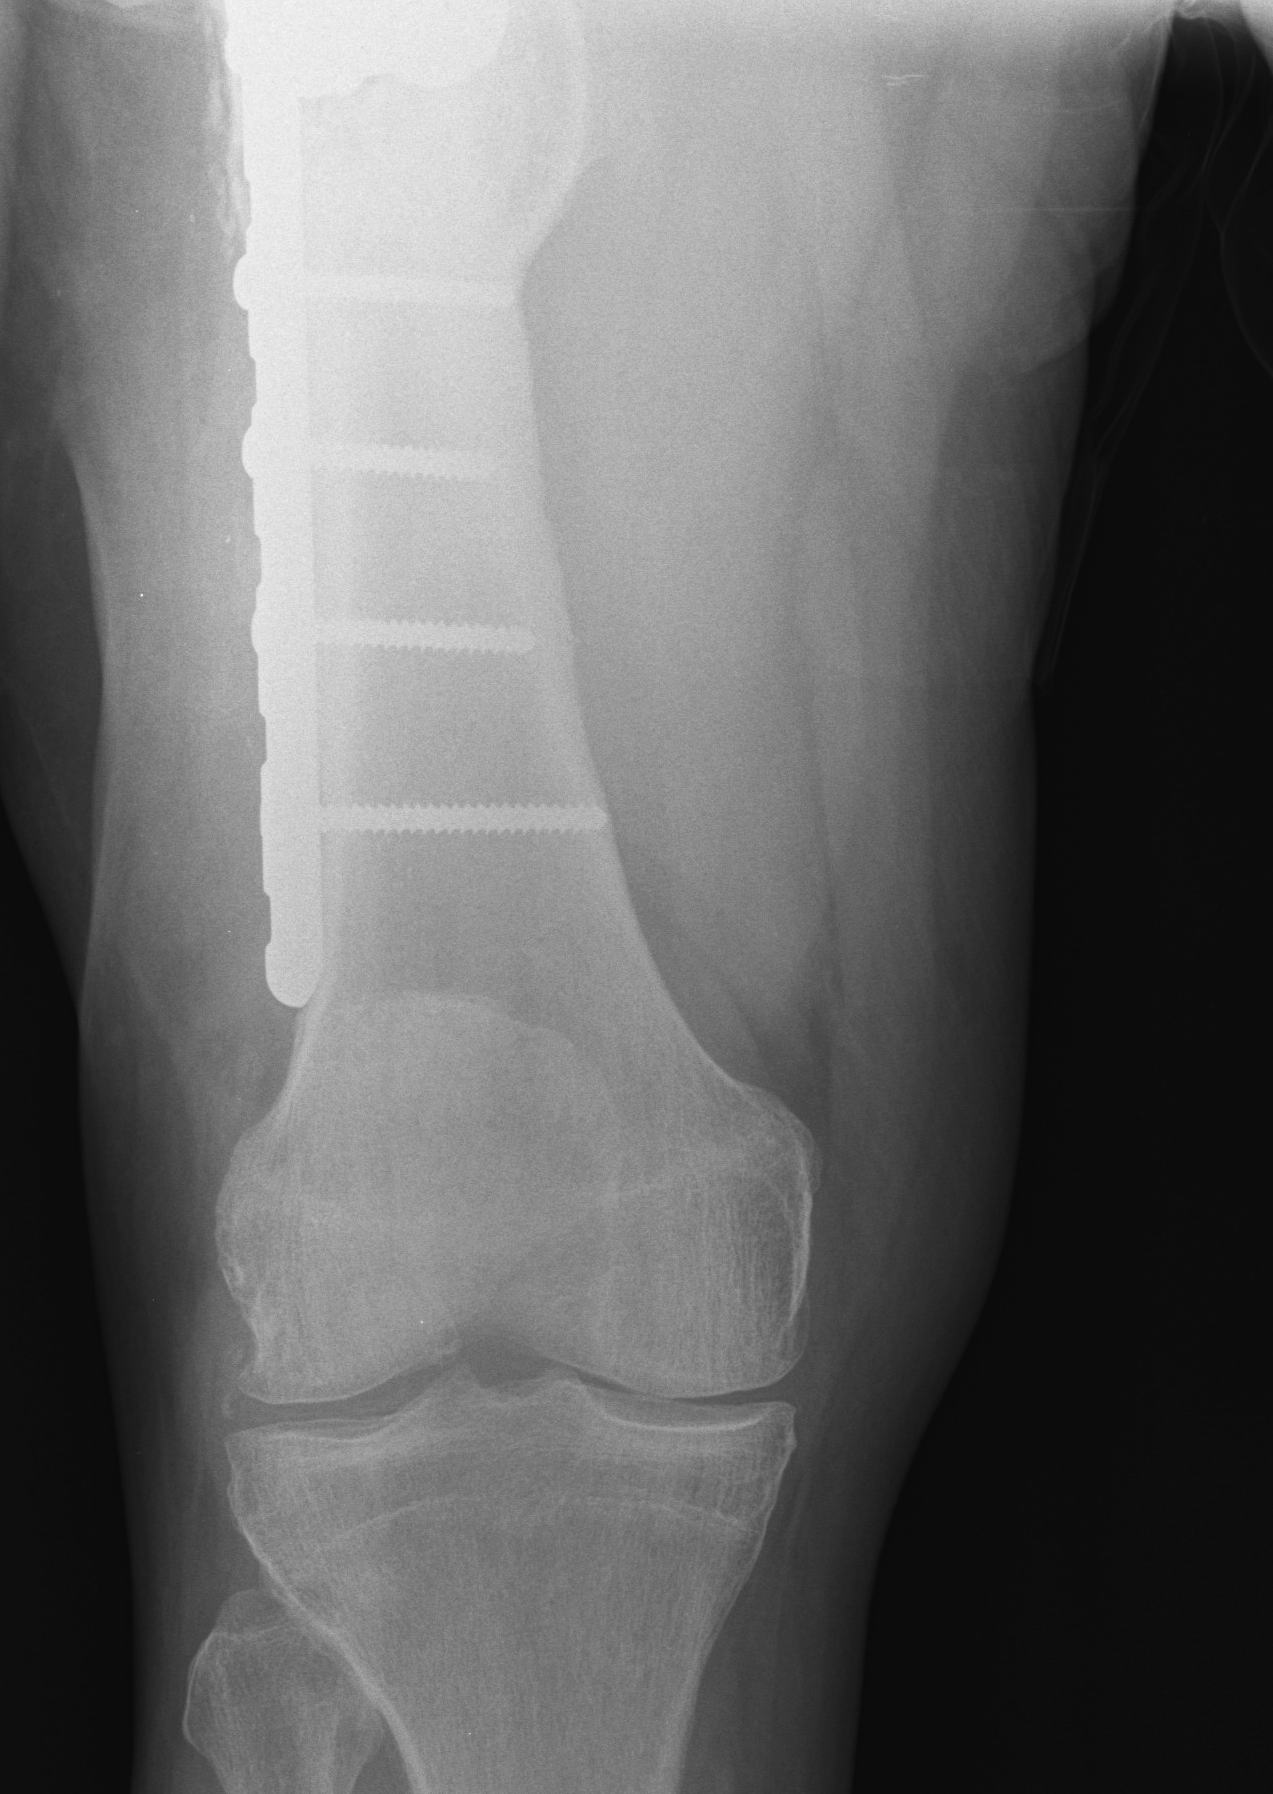

Indications

Unable to use femoral / tibial IM or EM Jigs

- fracture / metal work / deformity